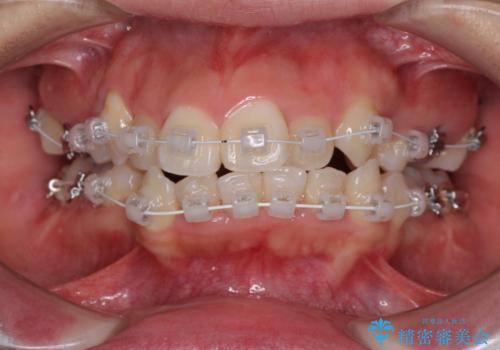

著しい叢生と顎骨のズレ ワイヤー装置による抜歯矯正

- 前歯の著しい叢生や八重歯を気にして来院された患者様です。

上下の顎がずれており、上下の正中は歯1本分の差がありました。

上下左右の小臼歯4本を抜歯し、極力正中を合わせるように矯正治療を始めていくこととしました。

咬み合わせの乱れが著しく、治療途中で一部反対咬合となってしまいました。

アンカーなどをうまく使用して、3年の期間を要してきれいに仕上げることができました。